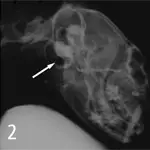

2. Normal feline tympanic bulla. Air shadow from external ear canal is superimposed on tympanic bulla.